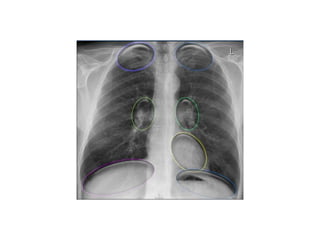

• Once you know how the normal hilar structures look like on

a lateral view, it is easier to detect abnormalities.

• In this case on the PA-view there is hilar enlargement.

On the PA-view it is not clear whether this is due to dilated

vessels or enlarged lymph nodes.

On the lateral view there are round structures in areas

where you don't expect any vessels. So we can conclude

that we are dealing with enlarged lymph nodes.

• This patient has sarcoidosis.

Notice also the widening of the paratracheal line (or stripe)

as a result of enlarged lymph nodes.

• The left hilum should never be lower than the right hilum.

• Enlargement of the hili is usually due to

lymphadenopathy or enlarged vessels.

• In this case there is an enlarged hilar shadow on

both sides.

This could be the result of enlarged vessels or

enlarged lymph nodes.

A very helpful finding in this case is the mass on

the right of the trachea.

• This is known as the 1-2-3 sign in sarcoidosis, i.e.

enlargement of left hilum, right hilum and

paratracheal.

hili • Once youknow how the normal hilar structures look like on a lateral view, it is easier to detect abnormalities. • In this case on the PA-view there is hilar enlargement. On the PA-view it is not clear whether this is due to dilated vessels or enlarged lymph nodes. On the lateral view there are round structures in areas where you don't expect any vessels. So we can conclude that we are dealing with enlarged lymph nodes. • This patient has sarcoidosis. Notice also the widening of the paratracheal line (or stripe) as a result of enlarged lymph nodes. • The left hilum should never be lower than the right hilum.

• Enlargement ofthe hili is usually due to lymphadenopathy or enlarged vessels. • In this case there is an enlarged hilar shadow on both sides. This could be the result of enlarged vessels or enlarged lymph nodes. A very helpful finding in this case is the mass on the right of the trachea. • This is known as the 1-2-3 sign in sarcoidosis, i.e. enlargement of left hilum, right hilum and paratracheal.